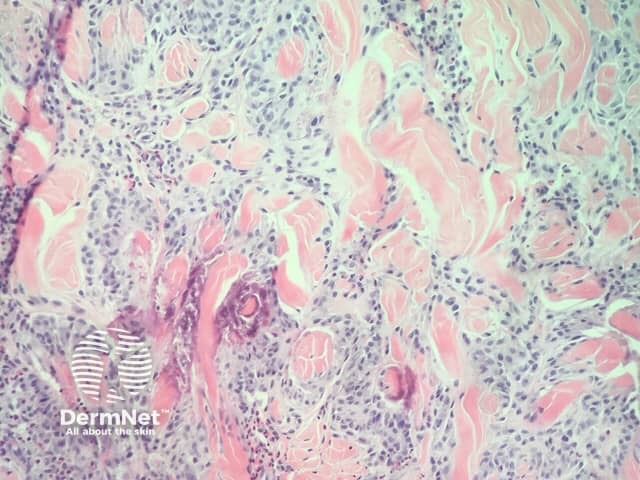

In eosinophilic granulomatosis with polyangiitis, the histopathology is varied depending on the stage of the disease and the type of lesion biopsied. Usually, the presentation in the skin occurs in the later stages of the disease and the prominent features include tissue eosinophilia (often with eosinophilic deposition 'flame figures' on collagen fibres) and extravascular granulomas (figures 1–3). Later lesions characteristically show vasculitis, which involves small to medium-sized vessels in the dermis and subcutis.

Figure 1